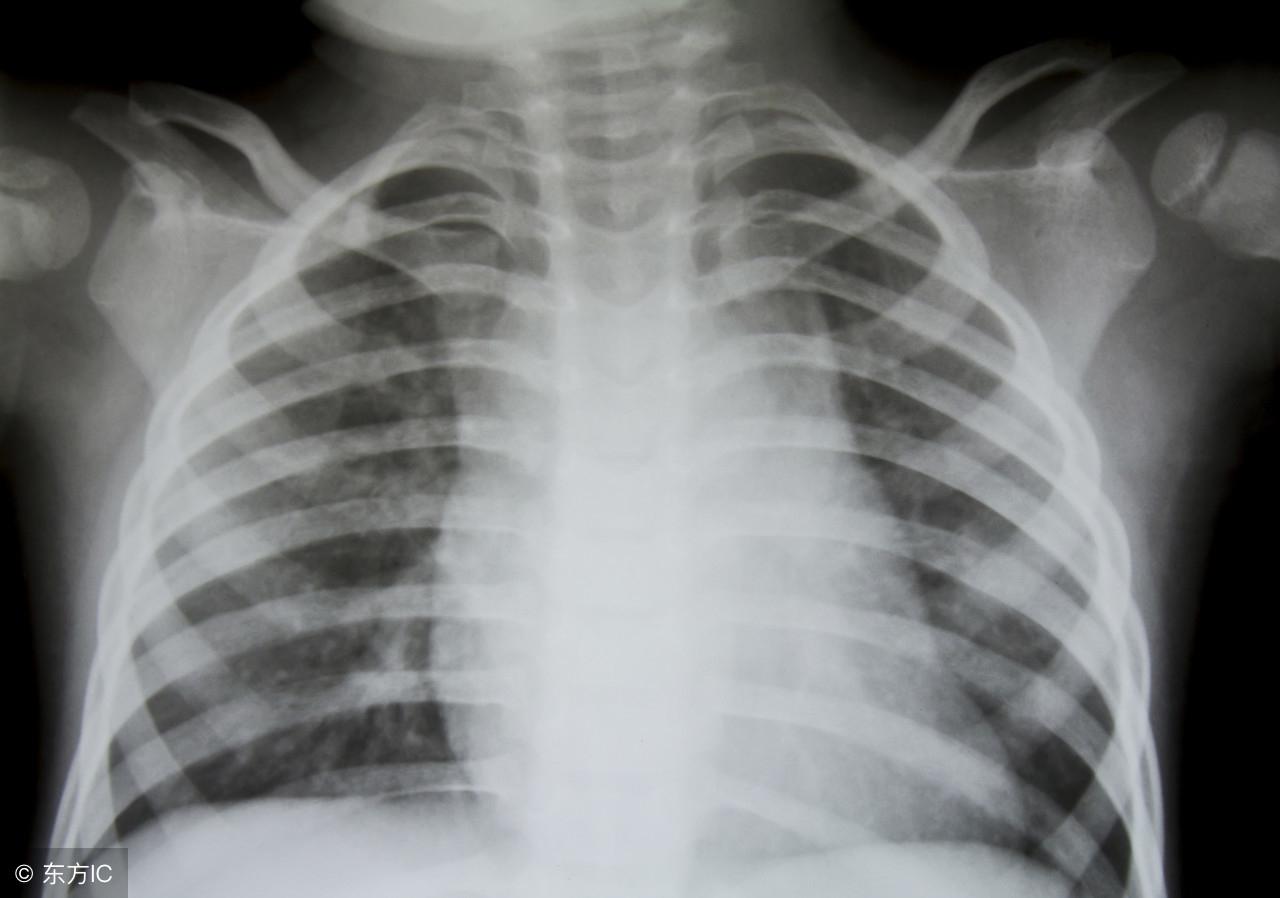

診斷慢性結腸炎主要依據(jù)患者的癥狀、體征及輔助檢查,醫(yī)生會根據(jù)患者的病史、體檢結果,結合相關實驗室檢查、影像學檢查等綜合分析,作出診斷,常用的輔助檢查包括:

3、結腸鏡檢查:直接觀察結腸黏膜病變情況,取活檢進行病理學檢查,以確診慢性結腸炎。

4、鋇餐灌腸:通過鋇劑在腸道內的分布情況,了解腸道功能及病變情況。